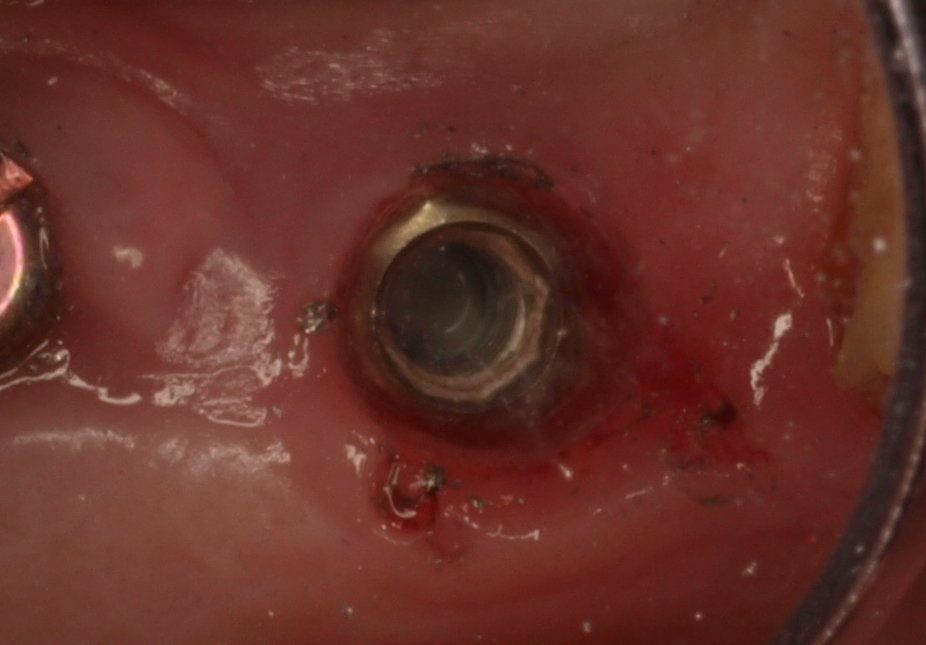

Paciente acude tras la colocación de un implante postextración hace mas de un año en una clínica a la cual no quiere volver por referir una mala experiencia. Tras la [...]